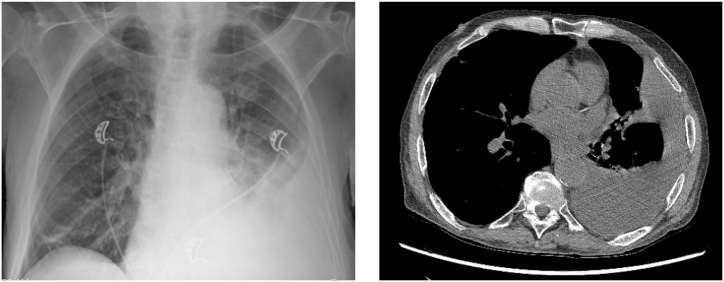

Pancreatopleural fistulas, rare complications of chronic pancreatitis, are often overlooked in the initial differential diagnoses of pleural effusions, resulting in delayed diagnosis and management. We present the case of an elderly male with recurrent pleural effusion and a history of chronic pancreatitis. Diagnostic challenges arose, with the initial misdiagnosis as pneumonia. Elevated pleural fluid amylase levels (11,370U/L) along with imaging findings led to the diagnosis of a pancreatopleural fistula. This case underscores the importance of considering uncommon etiologies in pleural effusions and highlights the significance of high pleural fluid amylase levels in diagnosing pancreatopleural fistulas.